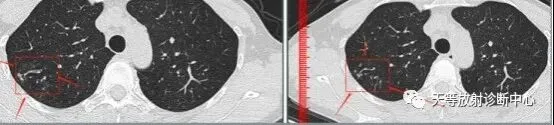

图2呼气状态:肺灌注不足,马赛克伪影,绿色区域出现类似磨玻璃影,HRCT尤其明显。

间接征象:病变小气道远端肺实质异常,主要表现为吸气相马赛克衰减和呼气相空气潴留。空气潴留表现为肺实质区域衰减增加程度低于正常,且无容积减少,边缘锐利,符合次级肺小叶轮廓。